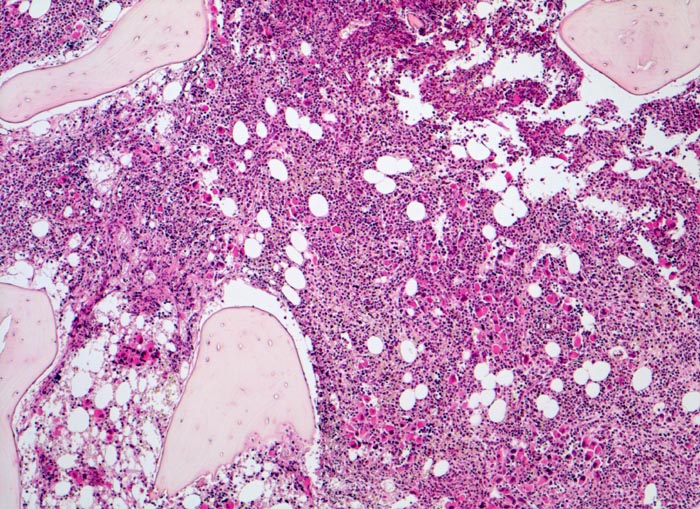

Die Erkrankung ist charakterisiert durch Knochenmarkfibrose, Hepato-Splenomegalie und extramedulläre Blutbildung. Diese findet sich am häufigsten in Leber und Milz, seltener in Lymphknoten, Nieren, Nebennieren, Dura mater, Gastrointestinaltrakt, Lunge, Mamma oder Haut. Blut und Knochenmark sind immer involviert. Die Krankheit entwickelt sich über ein initiales präfibrotisches Stadium mit hyperzellulärem Knochenmark zum fibrotischem Stadium (vorliegendes Präparat). Das fibrotische Stadium ist gekennzeichnet durch eine Vermehrung von Reticulin- und/oder Kollagenfasern und oft einer Knochenneubildung (=Osteomyelosklerose). Die Zellularität des Knochenmarks ist dann vermindert und dilatierte Marksinus enthalten intraluminale Blutbildungsherde. Es besteht eine auffallende Proliferation von Gruppen bildenden atypischen Megakaryozyten.

- Osteosklerose: verplumpte und breite Knochenbälkchen.

- Kollagenfibrose.

- Dilatierte Sinusoide mit intrasinusoidaler Blutbildung.

- Vermehrung von atypischen, in Gruppen liegenden Megakaryozyten mit abnorm lobulierten Kernen.

- Nacktkernige (zytoplasmaarme) und vergrösserte Megakaryozyten.

- Hyperplastische ausreifende Myelopoese.

- Hypoplastische Erythropoese.

- Retikulinfaserfibrose des Marks vorhanden aber in der HE Färbung schwierig quantifizierbar.